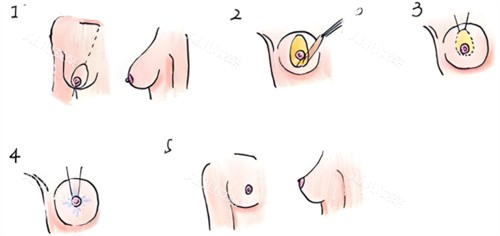

核心原理:筋膜层复位+韧带加固

传统手术靠“拉皮”,把下垂的皮肤往上拽,但皮肤有弹性极限,拽得越紧,反弹越快。维维提升的“狠活”在于:通过3mm的小创口切口(比一粒米还小),用可吸收线材更准一些找到乳腺下的筋膜层和悬韧带。打个比方,就像给下垂的吊灯重新挂好挂钩——不是单纯拉绳子,而是加固吊灯的支架,让胸部从“软塌塌”变成“有筋骨”。

低创伤:3mm切口 vs 10cm长疤

传统乳房悬吊术需要在乳晕和下皱襞开双切口,总长度8-10cm,术后疤痕像“两条蜈蚣”。维维提升的切口仅2.5-3cm,藏在乳晕边缘,色素遮盖+精细缝合,6个月后疤痕淡化为一条浅浅的白线,穿比基尼、低领衣服完全无压力。